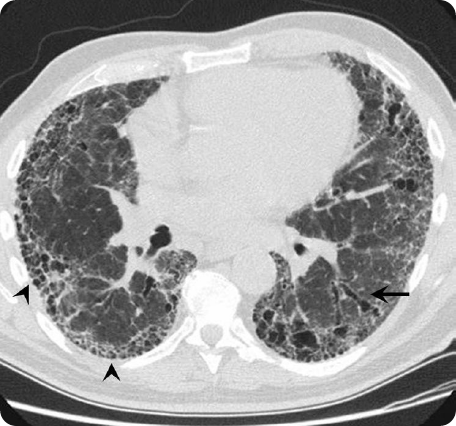

HRCT scan of an IPF patient. Adapted from Meltzer & Noble Orphanet Journal of Rare Diseases 2008.